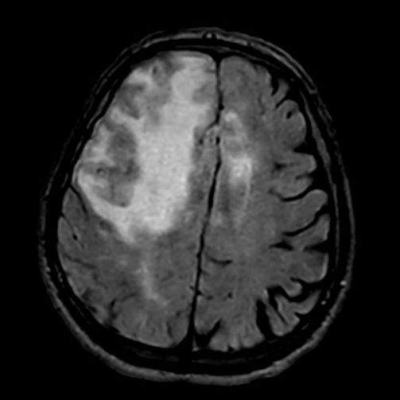

77 Y, E

1 aydır sol kol ve bacakta güçsüzlük, konfüzyon

Enfeksiyon markerları negatif

Serebral Amiloid Anjiyopatiye ile ilişkili inflamasyon (CAA-ri)

Serebral amiloid anjiopati ilişkili inflamasyon